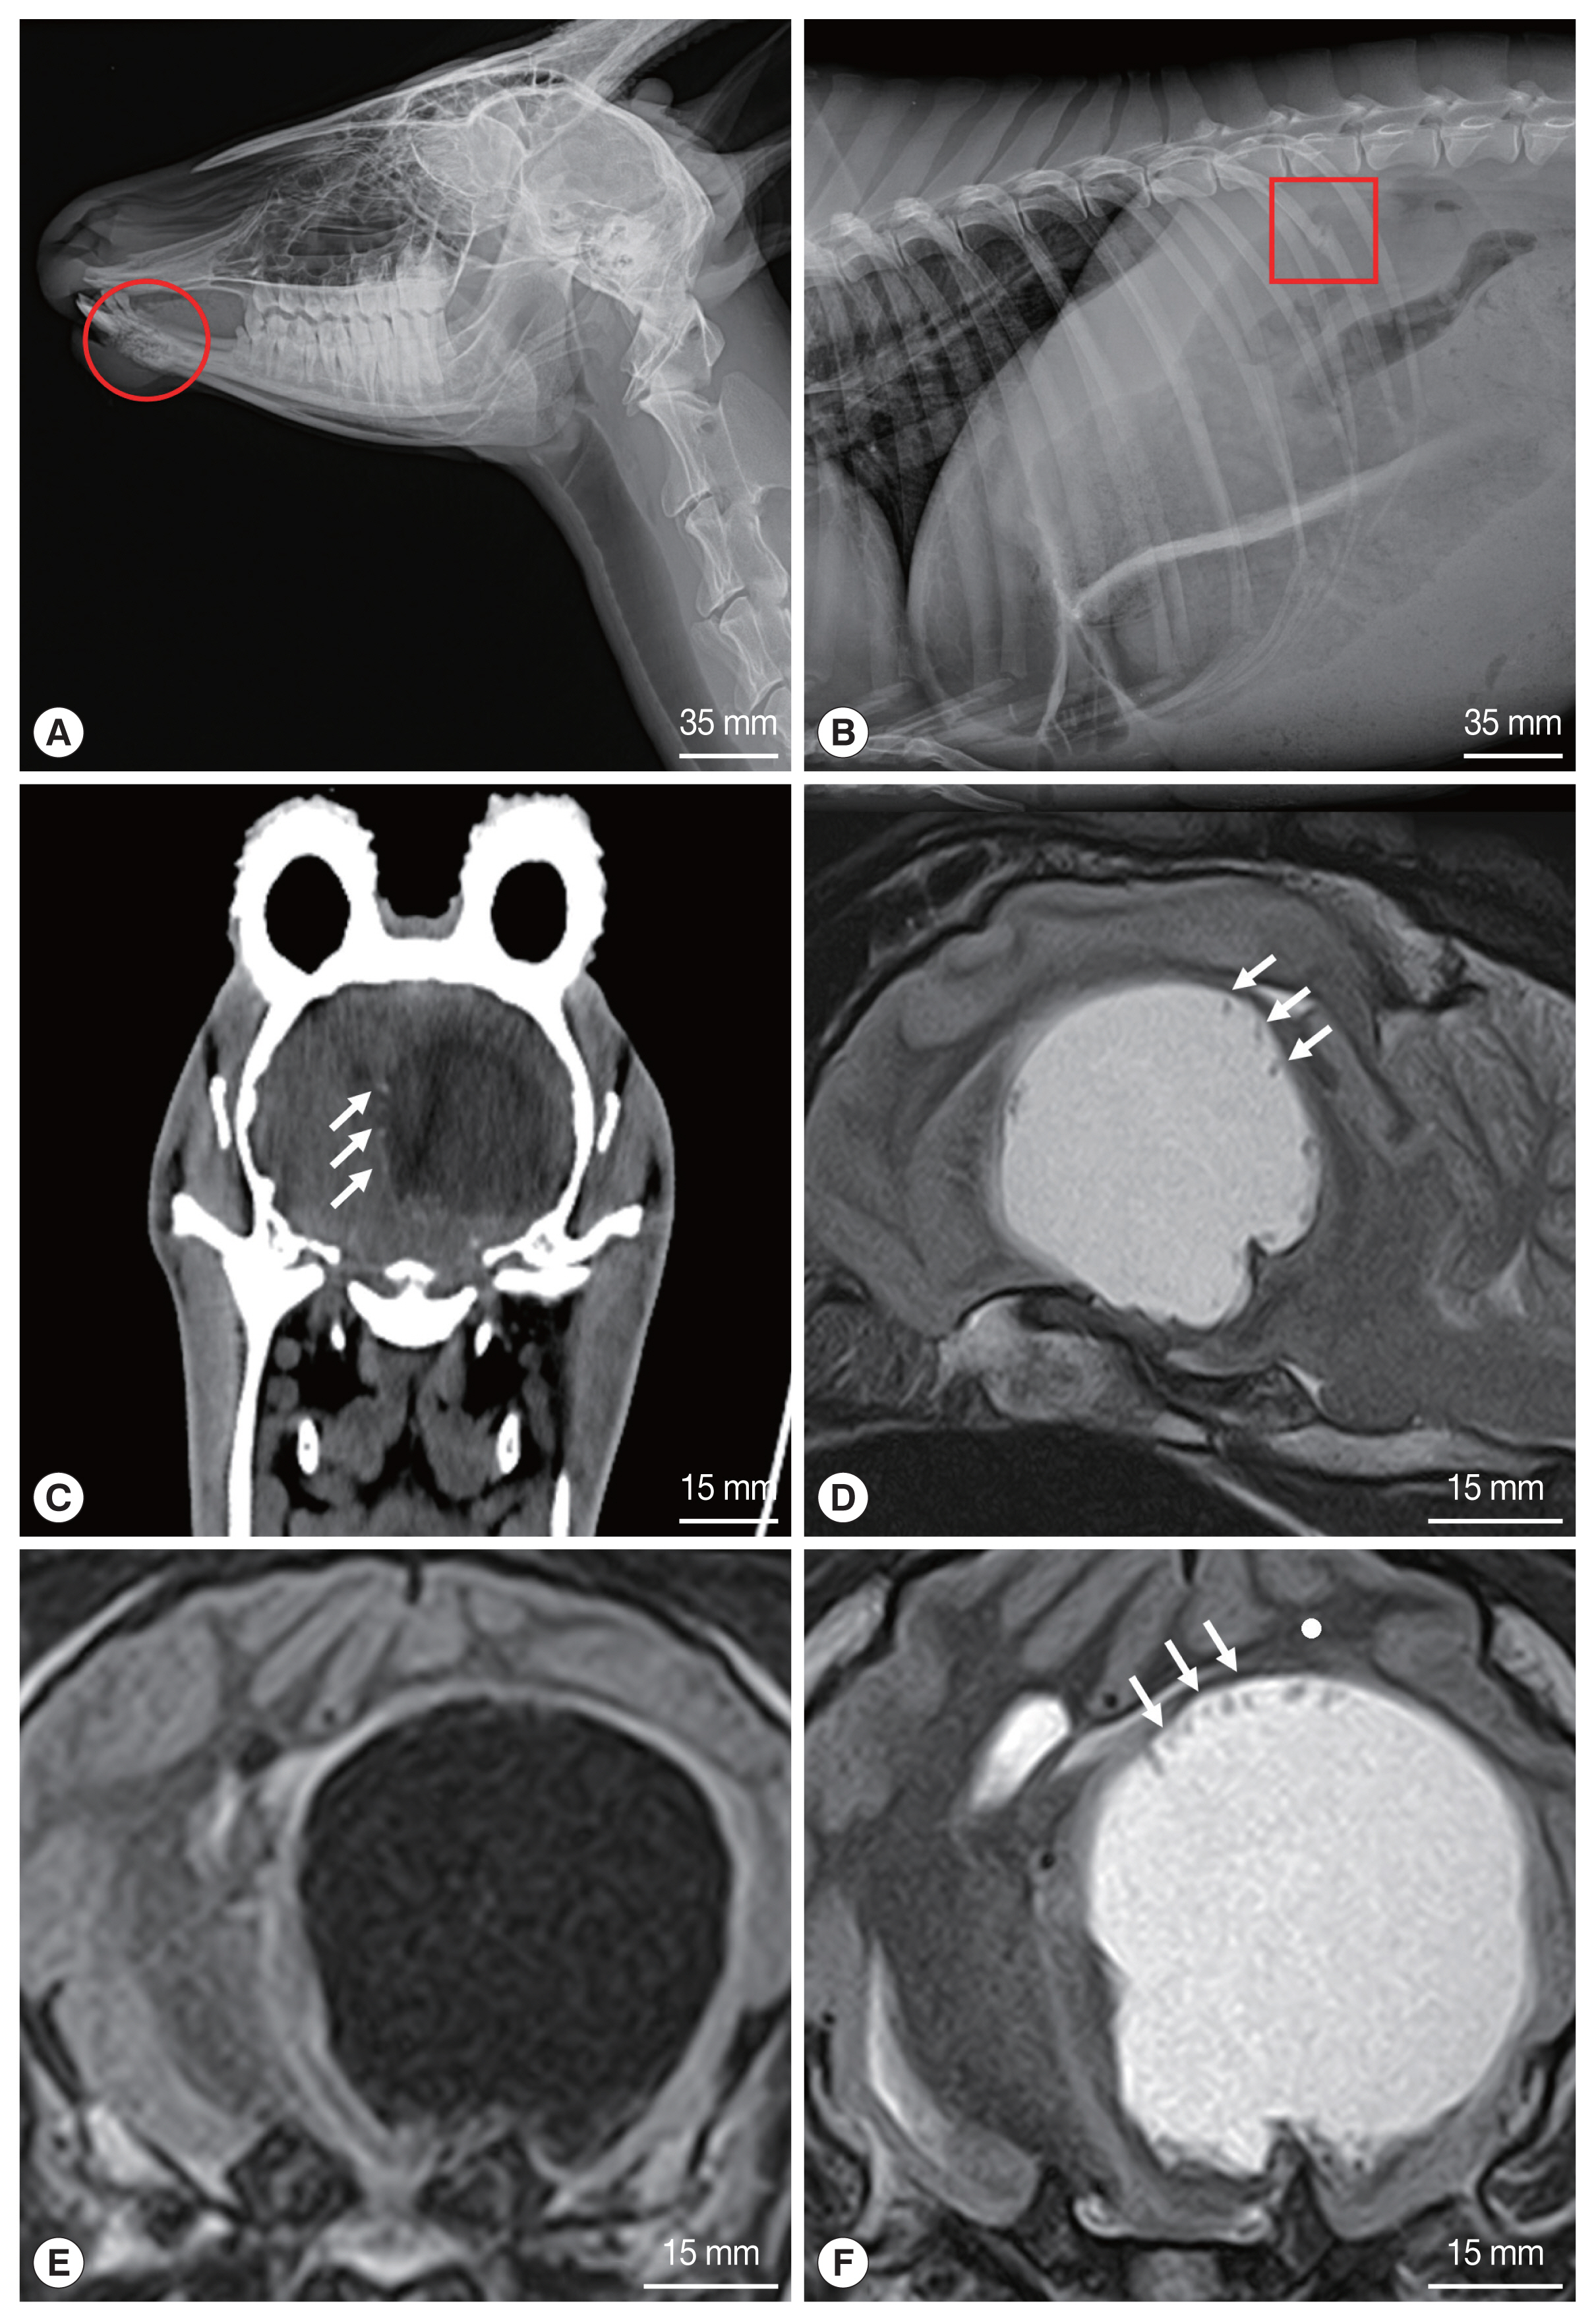

Radiographs of the goral revealed osteolysis of the mandible, fracture of the right 13th rib, and severe pneumonia (Fig. 1A, B). Based on the radiographic findings, the goral was judged to have met a traffic accident (TA), and accordingly treatment was initiated, but the neurological symptoms persisted. CT and MRI of the brain were performed using standard procedures because the neurological symptoms did not improve despite treatment. The goral was positioned in sternal recumbency for CT and MRI examinations. CT scanning was performed using a Somatom Emotion 6 (Siemens, Erlangen, Germany). MRI was performed by a 1.5 T unit (Vantage Elan™, Toshiba, Tokyo, Japan), using a combination of the 16 channel flexible coil (16-channel Flex SPEEDER Large®, Toshiba, Tokyo, Japan) and spine coil (Octave SPEEDER Spine®, Toshiba, Tokyo, Japan). In the CT images, the parasitic cyst (3.1×3.1 cm) was seen as a spherical structure with hypodensity in the left cerebral hemisphere (Fig. 1C). Faint hyperdense structures were also observed at the peripheral margin of the cyst, which were invaginated on the cyst wall (Fig. 1C). MRI of the head demonstrated the presence of a cystic structure in the brain parenchyma of the left cerebral hemisphere (Fig. 1D–F). The cyst was irregular, round shaped and clearly distinguished from the brain parenchyma. The cyst appeared hypointense in the T1 weighted (T1W) image (Fig. 1E) and hyperintense in the T2 weighted (T2W) image (Fig. 1D, F). In the T2W image, hypodense structures were found at the peripheral edge of the cyst inner wall (Fig. 1D, F), but not in the T1W image. Two days after MRI scan, the goral’s clinical signs became severe with heavier breathing, shortness of breath, and eventually the goral died.

Other diagnostic methods such as CT and MRI have also been used to diagnose. CT was used in the diagnosis of coenurosis in humans and other animals. Several scholars have reported that the cyst appears to be a hypoattenuating structure with a mass effect in the CT images [10]. The MRI images of the brain parenchyma infected with Coenurus cerebralis appear hypointense in the T1W image and hyperintense in the T2W image [12]. CT and MRI are diagnostic methods that can accurately determine the exact location and size of the cyst. This information is essential for the surgical removal of the parasitic cysts [10]. In our case, hypointense cyst was detected in the left cerebral hemisphere on CT examination. In the T1W image, the cyst appeared hypointense, while in the T2W image it appeared hyperintense. In addition, the hypodense structures seen at the edge of the cyst inner wall on the CT and MRI images of gorals were determined to be protoscolices of C. cerebralis through post-mortem examination. To the best of our knowledge, in previous reported cases, protoscolices were frequently observed on CT, but not on MRI. However, protoscolices were observed in both MRI and CT in this study.